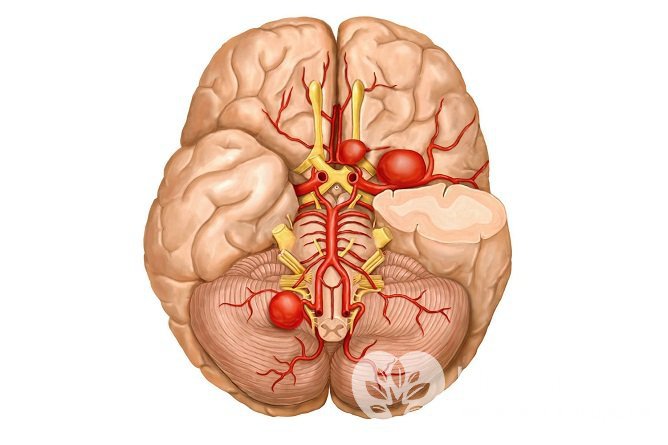

Аневризма сосудов головного мозга (внутричерепная аневризма, церебральная аневризма) – выпячивание артериальной стенки, обусловленное нарушением ее нормального трехслойного строения. Аневризма сосудов головного мозга локализуется в основном в местах разветвления артерий.

Выпячивание артериальной стенки сосуда головного мозгаНа сегодняшний день единой теории, объясняющей формирование названной сосудистой патологии, не существует. Большинство исследователей полагают, что аневризма головного мозга – многофакторная патология. К изменению строения стенки кровеносных сосудов могут приводить:

Несколько аневризм, расположенных на разных артерияхВ зависимости от формы аневризмы сосудов головного мозга могут быть веретенообразными и мешотчатыми. Вторая форма встречается примерно в 50 раз чаще, чем первая.

Аневризма сосудов головного мозга на МРТОбнаружение крови в цереброспинальной жидкости, полученной в ходе люмбальной пункции, – подтверждение разрыва аневризмы сосудов головного мозга.